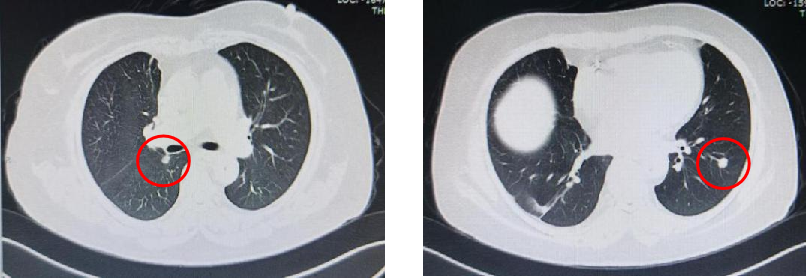

基本信息:性别 女,年龄 78岁,身高 159cm,体重 62kg。 主诉:结肠癌及肝转移瘤术后2年6个月(首次就诊时间为2018-09-10)。 既往史、个人史:“2型糖尿病”20年,予“二甲双胍 0.5g 口服 2次/日、门冬胰岛素注射液皮下注射,早 30U,晚 28U;甘精胰岛素皮下注射 20U ”降糖治疗,血糖控制一般。 家族史:无特殊。 02 初诊病史 体格检查、B超、CT及其他辅助检查。 体表面积1.60m,体格检查:浅表淋巴结未及肿大,双肺呼吸音粗,未闻及干湿性啰音,心律规整,未闻及杂音,腹壁可见陈旧性手术瘢痕,愈合良好,腹软,未及肿物,无压痛,肛查-,双下肢无水肿,起病隐匿,体检行腹部超声发现肝脏占位。 肠镜(2016-3-12):乙状结肠肿物。 咬检病理:(乙状结肠)腺癌。 肝胆胰增强CT(2016-3-10):肝左叶占位。 考虑:乙状结肠癌Ⅳ期 肝转移。 2016-3-21 于外院行“乙状结肠癌根治术+肝左叶转移瘤切除术”,术中予输血治疗,术后恢复慢,切口延期愈合。 术后病理:结肠中分化腺癌伴坏死形成,大者3.5cm×3.2cm×0.5cm,癌组织侵及浆膜脂肪层,脉管内癌栓形成,小者1cm×1cm×0.5cm,癌组织侵及粘膜下层。肠壁周围淋巴结癌转移(3/6),T3N1M1。(肝左叶)肝脏转移性腺癌伴大片坏死形成,大小6.6cm×6cm×4.5cm,结肠来源,残端及吻合口上下缘肠壁未见肿瘤侵及。 基因检测:KRAS、NRAS、BRAF 均未见突变。 初步诊断:乙状结肠癌Ⅳ期(pT3N1M1),同时性肝转移,中分化腺癌,2型糖尿病。 03 治疗方案 2016-4 XELOX 方案化疗1周期(具体剂量不详)因不良反应较重,未完成术后辅助治疗疗程。未予后续治疗,定期复查,病情稳定 胸腹CT(2017-3-19 ):右肺下叶新结节,考虑转移;肝左外叶转移瘤切除术后改变。 2017-4-1 于外院行局部肺肿物射频消融术,无治疗反应,恢复良好。 胸CT(2017-12-5):肺部新发结节,考虑转移。 【一线治疗方案(2017-12至2018-9)】 卡培他滨 1.5g po d1-14 q3w,共10个周期。 不良反应:1度消化道反应。 期间疗效评价:SD。 胸腹增强CT(2018-9-11):符合结肠癌切除术后,肝左叶切除后改变,双肺多发结节,部分较前增大。 2017-12-5 2018-9-11 建议调整方案治疗,患者家属拒绝,继续口服卡培他滨至2019年3月。 疗效评估: ECOG PS评分1分,新发活动后胸闷、气短症状 胸腹平扫CT(2019-3-26):双肺多发结节,较前增大;肝左外叶转移瘤切除术后改变。 2018-9-11 2019-3-26 评估PD。 【二线治疗方案(2019-4至2020-5)】 贝伐珠单抗 300mg ivgtt d0(体重62kg); 卡培他滨 1.5g po d1-14 q3w,共15周期。 不良反应:1级高血压、1度消化道反应。 疗效评估: 胸腹CT(2020-5-21):符合结肠癌术后、肝左叶切除术后,肝左切缘旁异常密度灶,左髂总动脉旁淋巴结;双肺多发结节,部分较前增大,右肺门肿物较前增大。 疗效评价:PD。 【三线治疗方案(2020-5至2020-10)】 西妥昔单抗 600mg ivgtt d0(体表面积1.66 m2); 亚叶酸钙 500mg ivgtt d1; 氟尿嘧啶 500mg ivgtt ,随后3500mg iv泵入 q2w,共9周期。 不良反应:无皮疹、腹泻、恶心、呕吐等。 疗效评估: 胸腹平扫CT(2020-09-07):右肺下叶背段软组织肿块,较前略减小,双肺多发小结节,转移瘤,同前;结肠癌术后、肝左叶切除术后改变,肝左切缘旁异常密度灶同前相仿,腹膜后左侧髂总动脉旁淋巴结同前。 2020-7-23 2020-9-7 疗效评价:SD(缩小趋势)。 胸腹平扫CT(2020-10-24):右肺下叶背段软组织肿块,较前(2020-9-7)略减小,双肺多发小结节,转移瘤,部分较前减小,结肠癌术后、肝左叶切除术后改变,肝左切缘旁异常密度灶同前相仿,腹膜后左侧髂总动脉旁淋巴结同前。 2020-9-7 2020-10-24 疗效评价:SD(缩小趋势)。 胸腹平扫CT(2020-12-13):右肺下叶背段软组织肿块,较前(2020-10-24)未见著变,双肺多发小结节,转移瘤,较前未见著变,结肠癌术后、肝左叶切除术后改变,肝左切缘旁异常密度灶同前相仿,腹膜后左侧髂总动脉旁淋巴结同前。 2020-12-13 疗效评价:SD。 患者未规律返院行西妥昔单抗维持治疗。 胸腹增强CT(2021-1-5):右肺下叶背段软组织肿块,较前(2020-12-13)增大,双肺多发小结节,转移瘤,左肺尖结节较前增大,余未见著变,左侧髂总动脉旁淋巴结较前增大。 疗效评价:PD。 【四线治疗方案(2021-1至2021-10)】 安罗替尼 8mg po 1次/日 d1-14 (2021-3 起因高血压2级,药物控制不佳调整为8mg qod ); 卡培他滨 1g po 2次/日 d1-14 q3w (2021-4 起因乏力2级不能耐受停服)。 不良反应:2级高血压,2级乏力,1级胆红素升高,1度消化道反应。 疗效评估: 胸腹增强CT(2021-10-3):右肺下叶背段占位,考虑恶性肿瘤,较前增大,双肺多发转移瘤,部分较前略增大,结肠癌术后、直肠区肠管明显扩张,肝左叶切除术后改变,切缘旁占位伴肝内胆管扩张,累及胆总管,考虑恶性病变,较前增大,腹膜后左侧髂总动脉旁淋巴结,较前增大,累及左侧输尿管伴以上输尿管及肾盂扩张。 2021-10-3 疗效评价:PD。 疗效评估: 胸腹增强CT(2021-10-3):右肺下叶背段占位,考虑恶性肿瘤,较前增大,双肺多发转移瘤,部分较前略增大,结肠癌术后、直肠区肠管明显扩张,肝左叶切除术后改变,切缘旁占位伴肝内胆管扩张,累及胆总管,考虑恶性病变,较前增大,腹膜后左侧髂总动脉旁淋巴结,较前增大,累及左侧输尿管伴以上输尿管及肾盂扩张。 【后线治疗方案(2021-10至2021-11)】 曲氟尿苷替匹嘧啶片(TAS-102) 40mg po 2次/日 d1-5,d8-12,q4w; 贝伐珠单抗 200mg ivgtt q2w。 不良反应:无皮疹、腹泻、恶心、呕吐等。 疗效评估: 胸腹增强CT(2021-11-17):右肺下叶背段占位,较前变化不明显,双肺多发转移瘤,较前变化不明显,结肠癌术后、直肠区肠管明显扩张,肝左叶切除术后改变,切缘旁占位伴肝内胆管扩张,累及胆总管,考虑恶性病变,较前变化不明显,腹膜后左侧髂总动脉旁淋巴结,较前减小,肾盂扩张较前减轻。 疗效评价:SD。 胸腹增强CT(2021-11-17):右肺下叶背段占位,较前变化不明显,双肺多发转移瘤,较前变化不明显,结肠癌术后、直肠区肠管明显扩张,肝左叶切除术后改变,切缘旁占位伴肝内胆管扩张,累及胆总管,考虑恶性病变,较前变化不明显,腹膜后左侧髂总动脉旁淋巴结,较前减小,肾盂扩张较前减轻。 04 病例小结 患者为高龄女性,诊断为直肠癌Ⅳ期多发转移,KRAS、NRAS、BRAF 均未见突变。 OS为69个月。